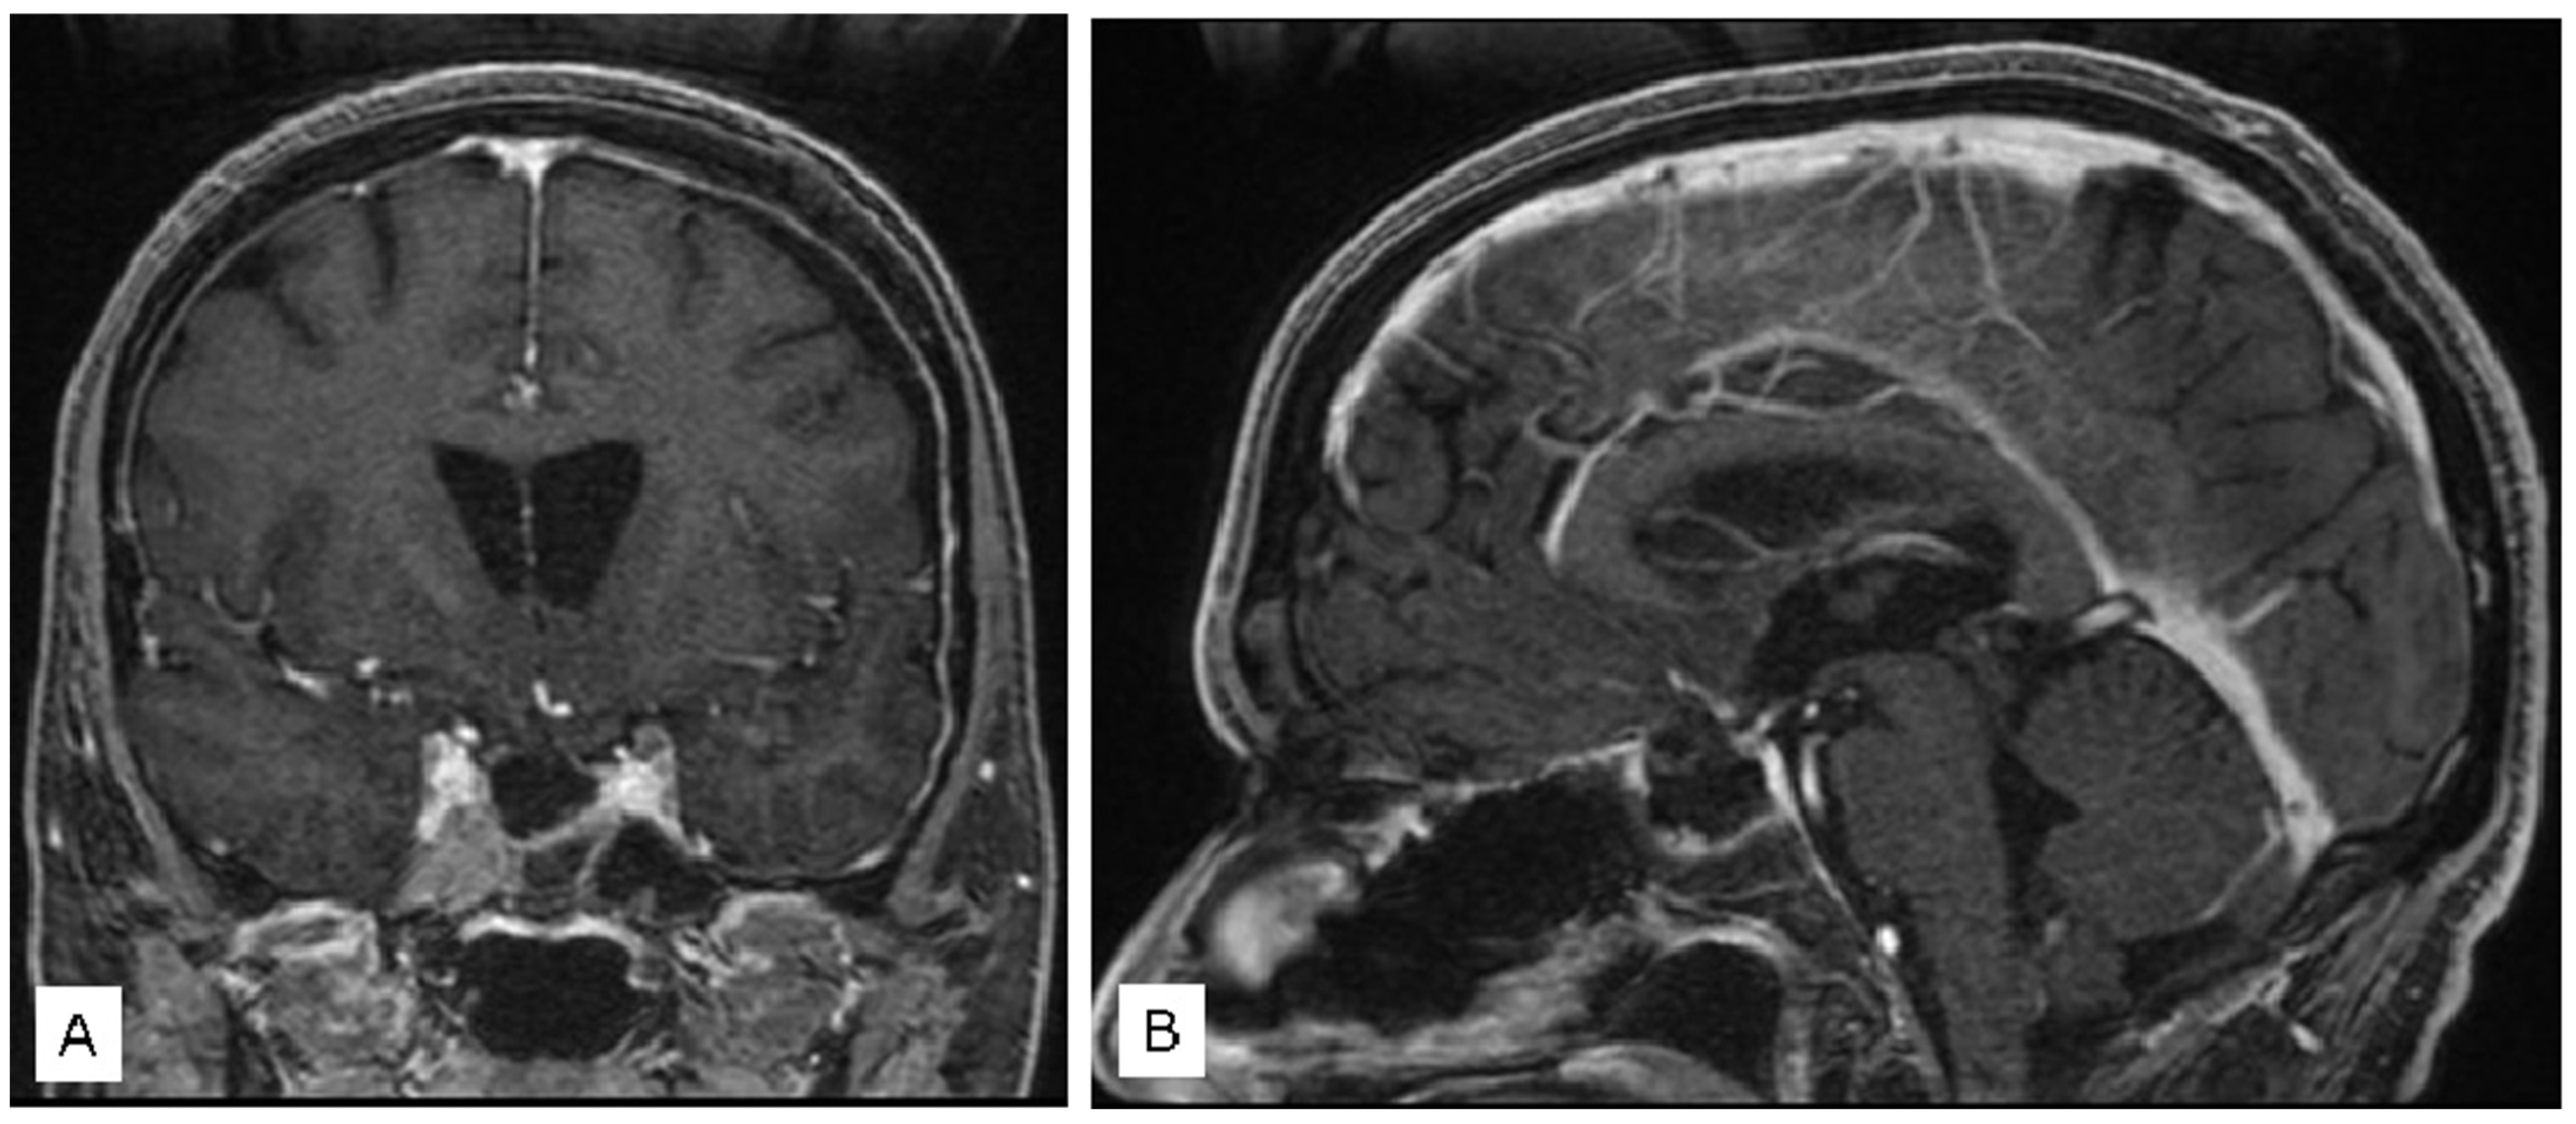

3.1.2. Case 2

3.1.3. Case 3